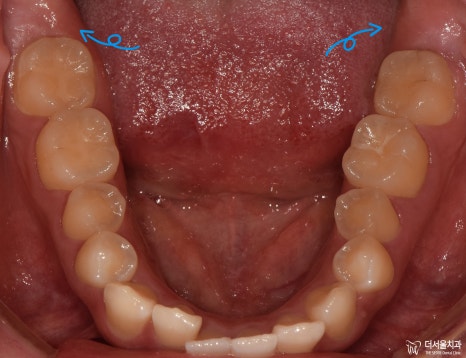

악궁이 좁으며 자리가 없었더라면,

발치를 진행해야 되었으나,

화살표에 표시된 것처럼

공간은 충분히 있었기에

그 자리에 있는 사랑니를 발치 후,

치아교정을 진행하여

안면 비대칭을 개선하는 것으로

잠실 치과 에서 치료 계획을 수립했습니다.